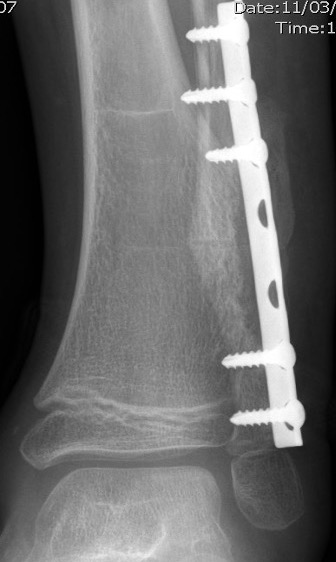

Ankle

Causes valgus deformity

- 19 patients with solitary osteochondroma of distal tibia or fibula

- cause plastic deformity and pronation deformity

- distal tibia more symptomatic than distal fibula

- 4/19 recurred

Appy-Fedida et al J Foot Ankle Surg 2017

- trans-fibular approach for worsening valgus deformity in 10 cases

- good functional outcomes

- recurrence in 1 case

- 7/10 developed tibiofibular synostosis